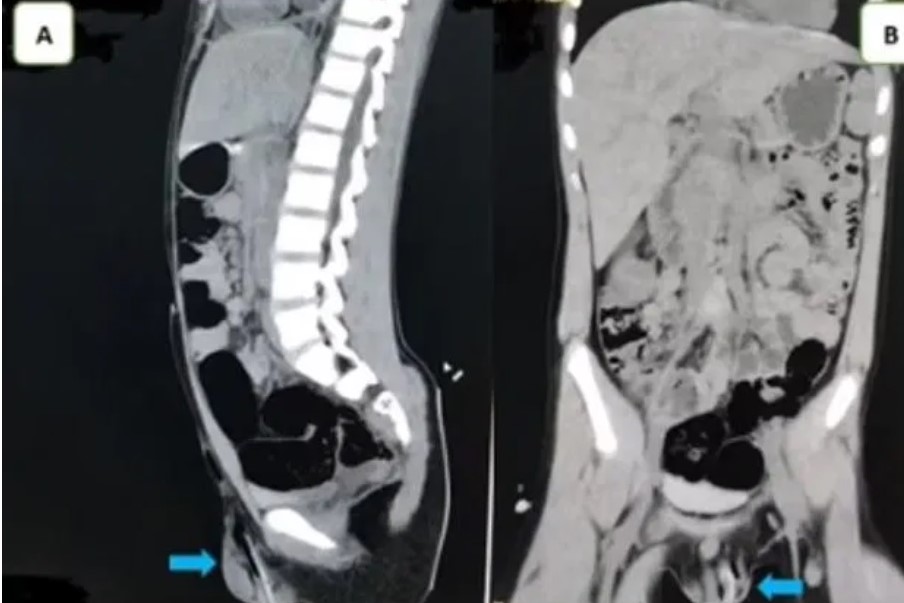

Gambar hasil imbasan doktor menunjukkan terdapat sebatang kayu menembusi bahagian bawah kiri skrotum kanak-kanak terbabit.

Doktor turut mengimbas bahagian tersebut bagi mengesahkan bahawa testikelnya tidak mengalami kerosakan sebelum mengeluarkan kayu tersebut.